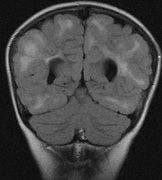

2. Subependymal nodules (SEN) are typically found along the lateral borders of the ventricles and parehncymal brain lesion (“cortical tubers”) (Figs. 14 and 15). Calcification in the first year of life is rare.132

On MRI imaging, the subependymal nodules and parenchymal brain lesions of infants (age ≤3 months) and adults show different signal characteristics. Infant CNS tubers are hyperintense on T1-weighted images and hypointense on T2-weighted images, which is the opposite of the pattern seen in adults.134 Malignant transformation of SEN occurs in about 10% to 15% of patients and the resultant subependymal giant cell astrocytoma accounts for 25% of premature deaths in TSC.135,136

Fig. 14. Tuberous Sclerosis Complex: Sub-Ependymal nodules. These are typically found along the lateral borders of the ventricles.132

Fig. 15. Tuberous Sclerosis Complex. (a) Patient 1: Axial CT scans demonstrating typical calcification of subependymal nodules in a 13-year-old girl with a history of seizures. (b and c) Patient 2. (b) Axial T2-weighted images demonstrate calcified subependymal nodules (arrowheads) and cortical tubers typical of tuberous sclerosis. (c) Widespread cortical tubers are seen on a coronal FLAIR sequence as thickening of the cortex and high signal of the subcortical white matter.